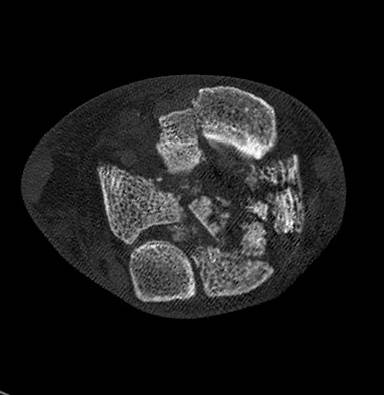

Aufnahmen im Computertomografen können eine sinnvolle Ergänzung sein, um die Begleitarthrosen darzustellen.